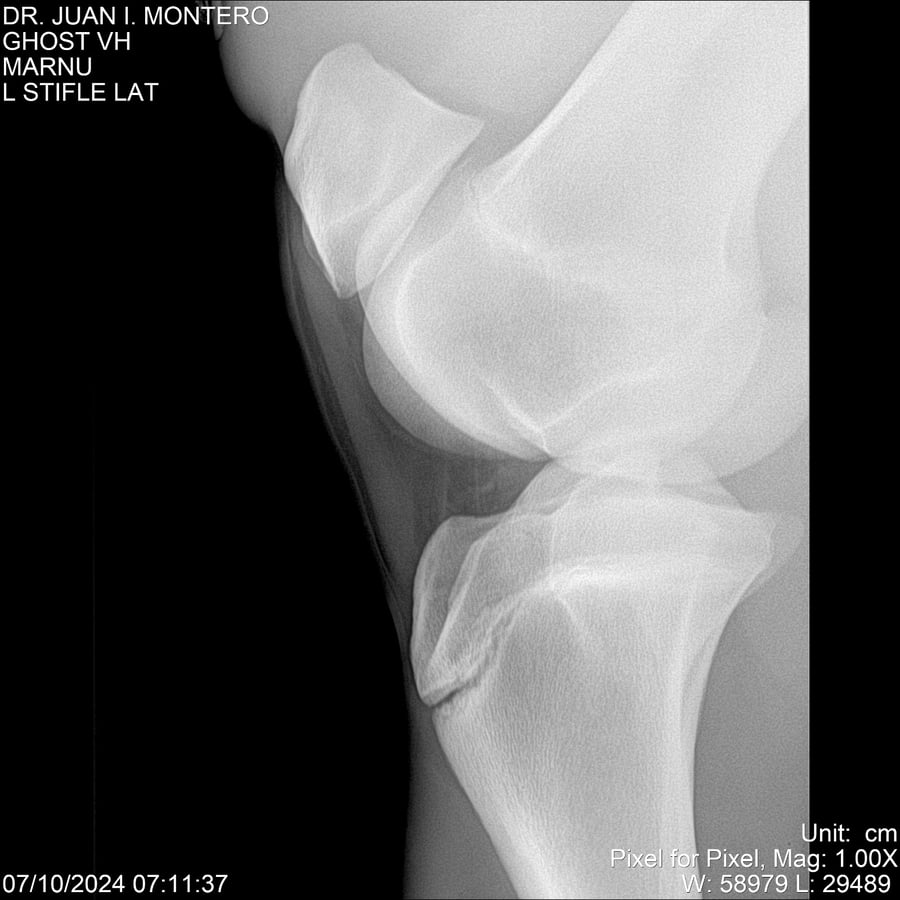

LOTE 15, GHOST VH 🔥 🔥 🔥 Lote Anterior Volver al remate Lote Siguiente Ficha Contacto Montevideo - Ficha del Lote Identificador: #282525 Categoría: Yeguarizos Montevideo - 69 Visualizaciones ClicData Contacto Empresa: Abelenda N. R., Walter Hugo Nombre*: Teléfono* : E-mail* : Mensaje Enviar Registrese gratis Este contenido Exclusivo está disponible sólo para usuarios registrados Ingresar